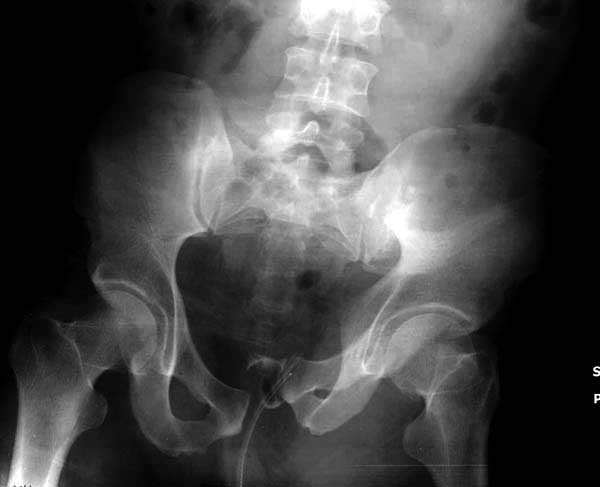

Здесь представлен случай 38 летнего больного (падение с высоты 9 метров) с нарушением тазового кольца. При поступлении для стабилизации передне-нижний аппарат наружной фиксации и на 6й день, вчера, операция из двух доступов.

Рецидив смещения - признак несостоятельности фиксации. В первую очередь из-за ранней нагрузки, или когда имеется нестабильность в тазовом кольце. При повреждениях транссакральных структур сзади, фиксация переднего полукольца-симфиза облегчает репозицию, но не гарантирует стабильность. Нестабильное тазовое кольцо ранее или поздно срывает фиксацию симфиза.